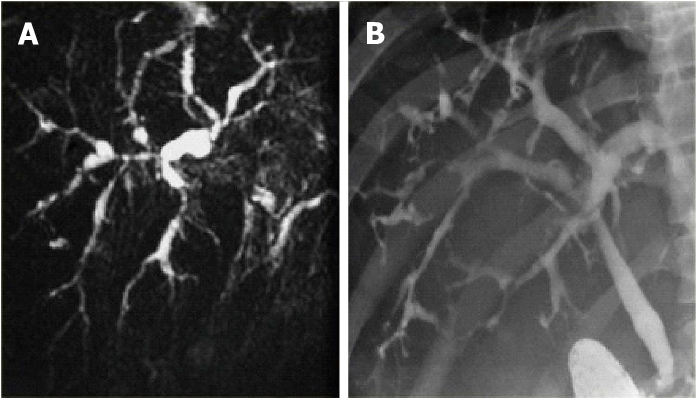

O diagnóstico da CEP normalmente é feito por colangiografia (endoscópica, transparietal ou por ressonância nuclear magnética, apesar da endoscópica ser a preferida). A biópsia hepática é importante no diagnóstico e para avaliar o grau da doença. Exames laboratoriais costumam mostrar aumento da fosfatase alcalina e as transminases quase sempre estão elevadas até 3 a 5 vezes o limite normal. As bilirrubinas podem se elevar à medida que a doença progride. Não há autoanticorpo característico, apesar do p-ANCA (anticorpo anticitoplasma de neutrófilos, padrão perinuclear) e ANA serem comuns (o p-ANCA está presente em 33 a 88% dos portadores de CEP).

| Colangiografia na CEP | ||

| Métodos | endoscópica (CPRE) | desconfortável ao paciente, mas com bons resultados |

| transparietal | invasivo, com risco de complicações e baixa eficácia na CEP | |

| ressonância nuclear magnética | não invasivo e seguro, mas muito caro e disponível em poucos lugares, não permite dilatação ou retirada de material para análise | |

| Achados típicos | estreitamento e irregularidade em vários pontos da via biliar (dentro e fora do fígado), com aspecto de “colar de contas” | |

| dilatação proeminente, massa polipóide e estreitamento progressivo sugerem colangiocarcinoma | ||

Apesar de invasiva, a biópsia hepática pode ser útil no diagnóstico e no prognóstico (avaliação do grau e previsão de complicações). Infelizmente, o grau da doença pode variar bastante em locais diferentes do fígado, prejudicando a eficácia do exame. Em pacientes com diagnóstico bem estabelecido da CEP, por exames laboratoriais e colangiografia, no entanto, a necessidade de realização da biópsia hepática vem sendo rediscutida.

Nos pacientes com doença em fase inicial, no entanto, as alterações histológicas geralmente são pouco características, a colangiografia freqüentemente é normal e os auto-anticorpos podem não ser encontrados. A falta de um exame suficientemente sensível e específico nessa fase pode prejudicar a realização do diagnóstico correto.

Um subgrupo de portadores de CEP apresenta a chamada “colangite esclerosante primária de pequenos ductos”, uma condição onde há alterações laboratoriais e histológicas típicas, mas não observam-se lesões na colangiografia. Esses pacientes tem características semelhantes em termos de auto-anticorpos e associação com doença inflamatória intestinal, mas aparentemente têm uma doença de evolução mais benigna.